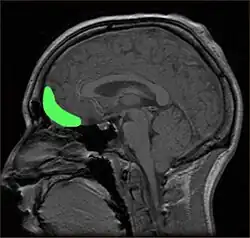

This case saw a man take a sudden, previously non-existent interest in child pornography, making sexual advances towards his step-daughter and staff at a sexual rehabilitation centre despite a strong contradiction to his own moral compass. He was subsequently sentenced to prison for child molestation. After experiencing strong headaches and an uneven gait, he underwent a neurological exam, revealing a tumour that had displaced his right orbitofrontal lobe.[3] The tumour was removed and mere hours later his behaviour and gait had returned to normal. Later, his sexual deviancy recommenced and he began to experience more headaches, with brain scans indicating the tumour had returned. After having it removed, he appeared to have been cured again.

To consider the neurological aspect of the aforementioned case study, we consider clinical psychologist Cantor's assessment of the culprit. He proposed that the tumour merely impeded the man’s decision making process, interfering with his ability to regulate his behaviour which had previously suppressed his internal paedophilic desires. Thus, with regards to free will and culpability, whether or not the man truly wanted to act on these sexual desires was irrelevant; he had no liberty to make a different choice given the composition of his brain, and therefore no had no free will.